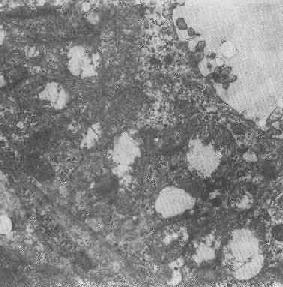

线粒体肿胀(基质型)空泡变(心肌缺氧)

图1-11 线粒体肿胀(基质型)空泡变(心肌缺氧)

2.大小改变 细胞损伤时最常见的改变为线粒体肿大。根据线粒体的受累部位可分为基质型肿胀和嵴型肿胀二种类型,而以前者为常见。基质型肿胀时线粒体变大变圆,基质变浅、嵴变短变少甚至消失(图1-9)。在极度肿胀时,线粒体可转化为小空泡状结构(图1-10,图1-11)。此型肿胀为细胞水肿的部分改变。光学显微镜下所谓的浊肿细胞中所见的细颗粒即肿大的线粒体。嵴型肿较少见,此时的肿胀局限于嵴内隙,使扁平的嵴变成烧瓶状乃至空泡状,而基质则更显得致密。嵴型肿胀一般为可复性,但当膜的损伤加重时,可经过混合型而过渡为基质型。

线粒体为对损伤极为敏感的细胞器,其肿胀可由多种损伤因子引起,其中最常见的为缺氧;此外,微生物毒素、各种毒物、射线以及渗透压改变等亦可引起。但轻度肿大有时可能为其功能升高的表现,较明显的肿胀则恒为细胞受损的表现。但只要损伤不过重、损伤因子的作用不过长,肿胀仍可恢复。